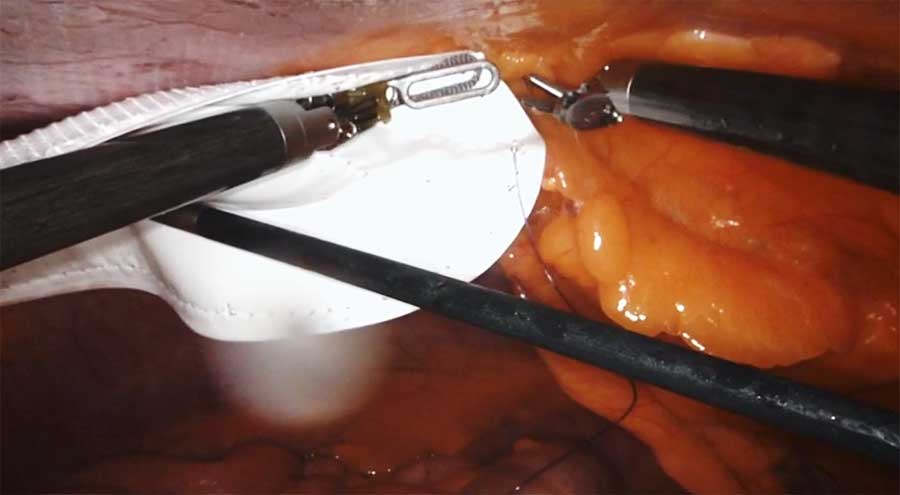

Robotic Ventral Hernia Repair With Primary Closure And Mesh Placement